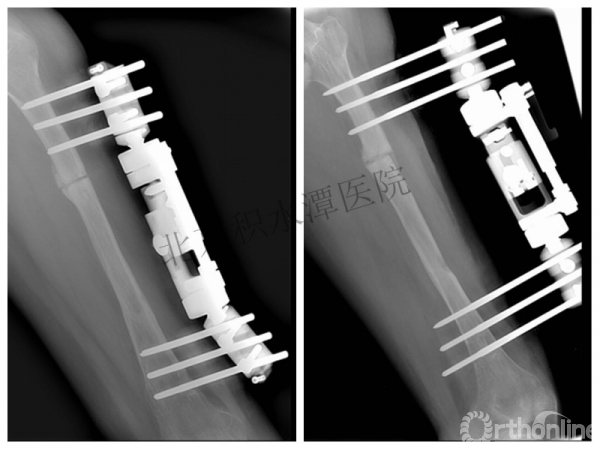

外固定架术后一年

整整11年!是否治疗终结?

病人的付出?医生当反思!

一、思考

1.使用了医生可以使用的所有固定方式

2.似乎哪一次的处理都没有违背原则

3.问题出在哪儿?

4.骨折治疗—手术不是万能的!